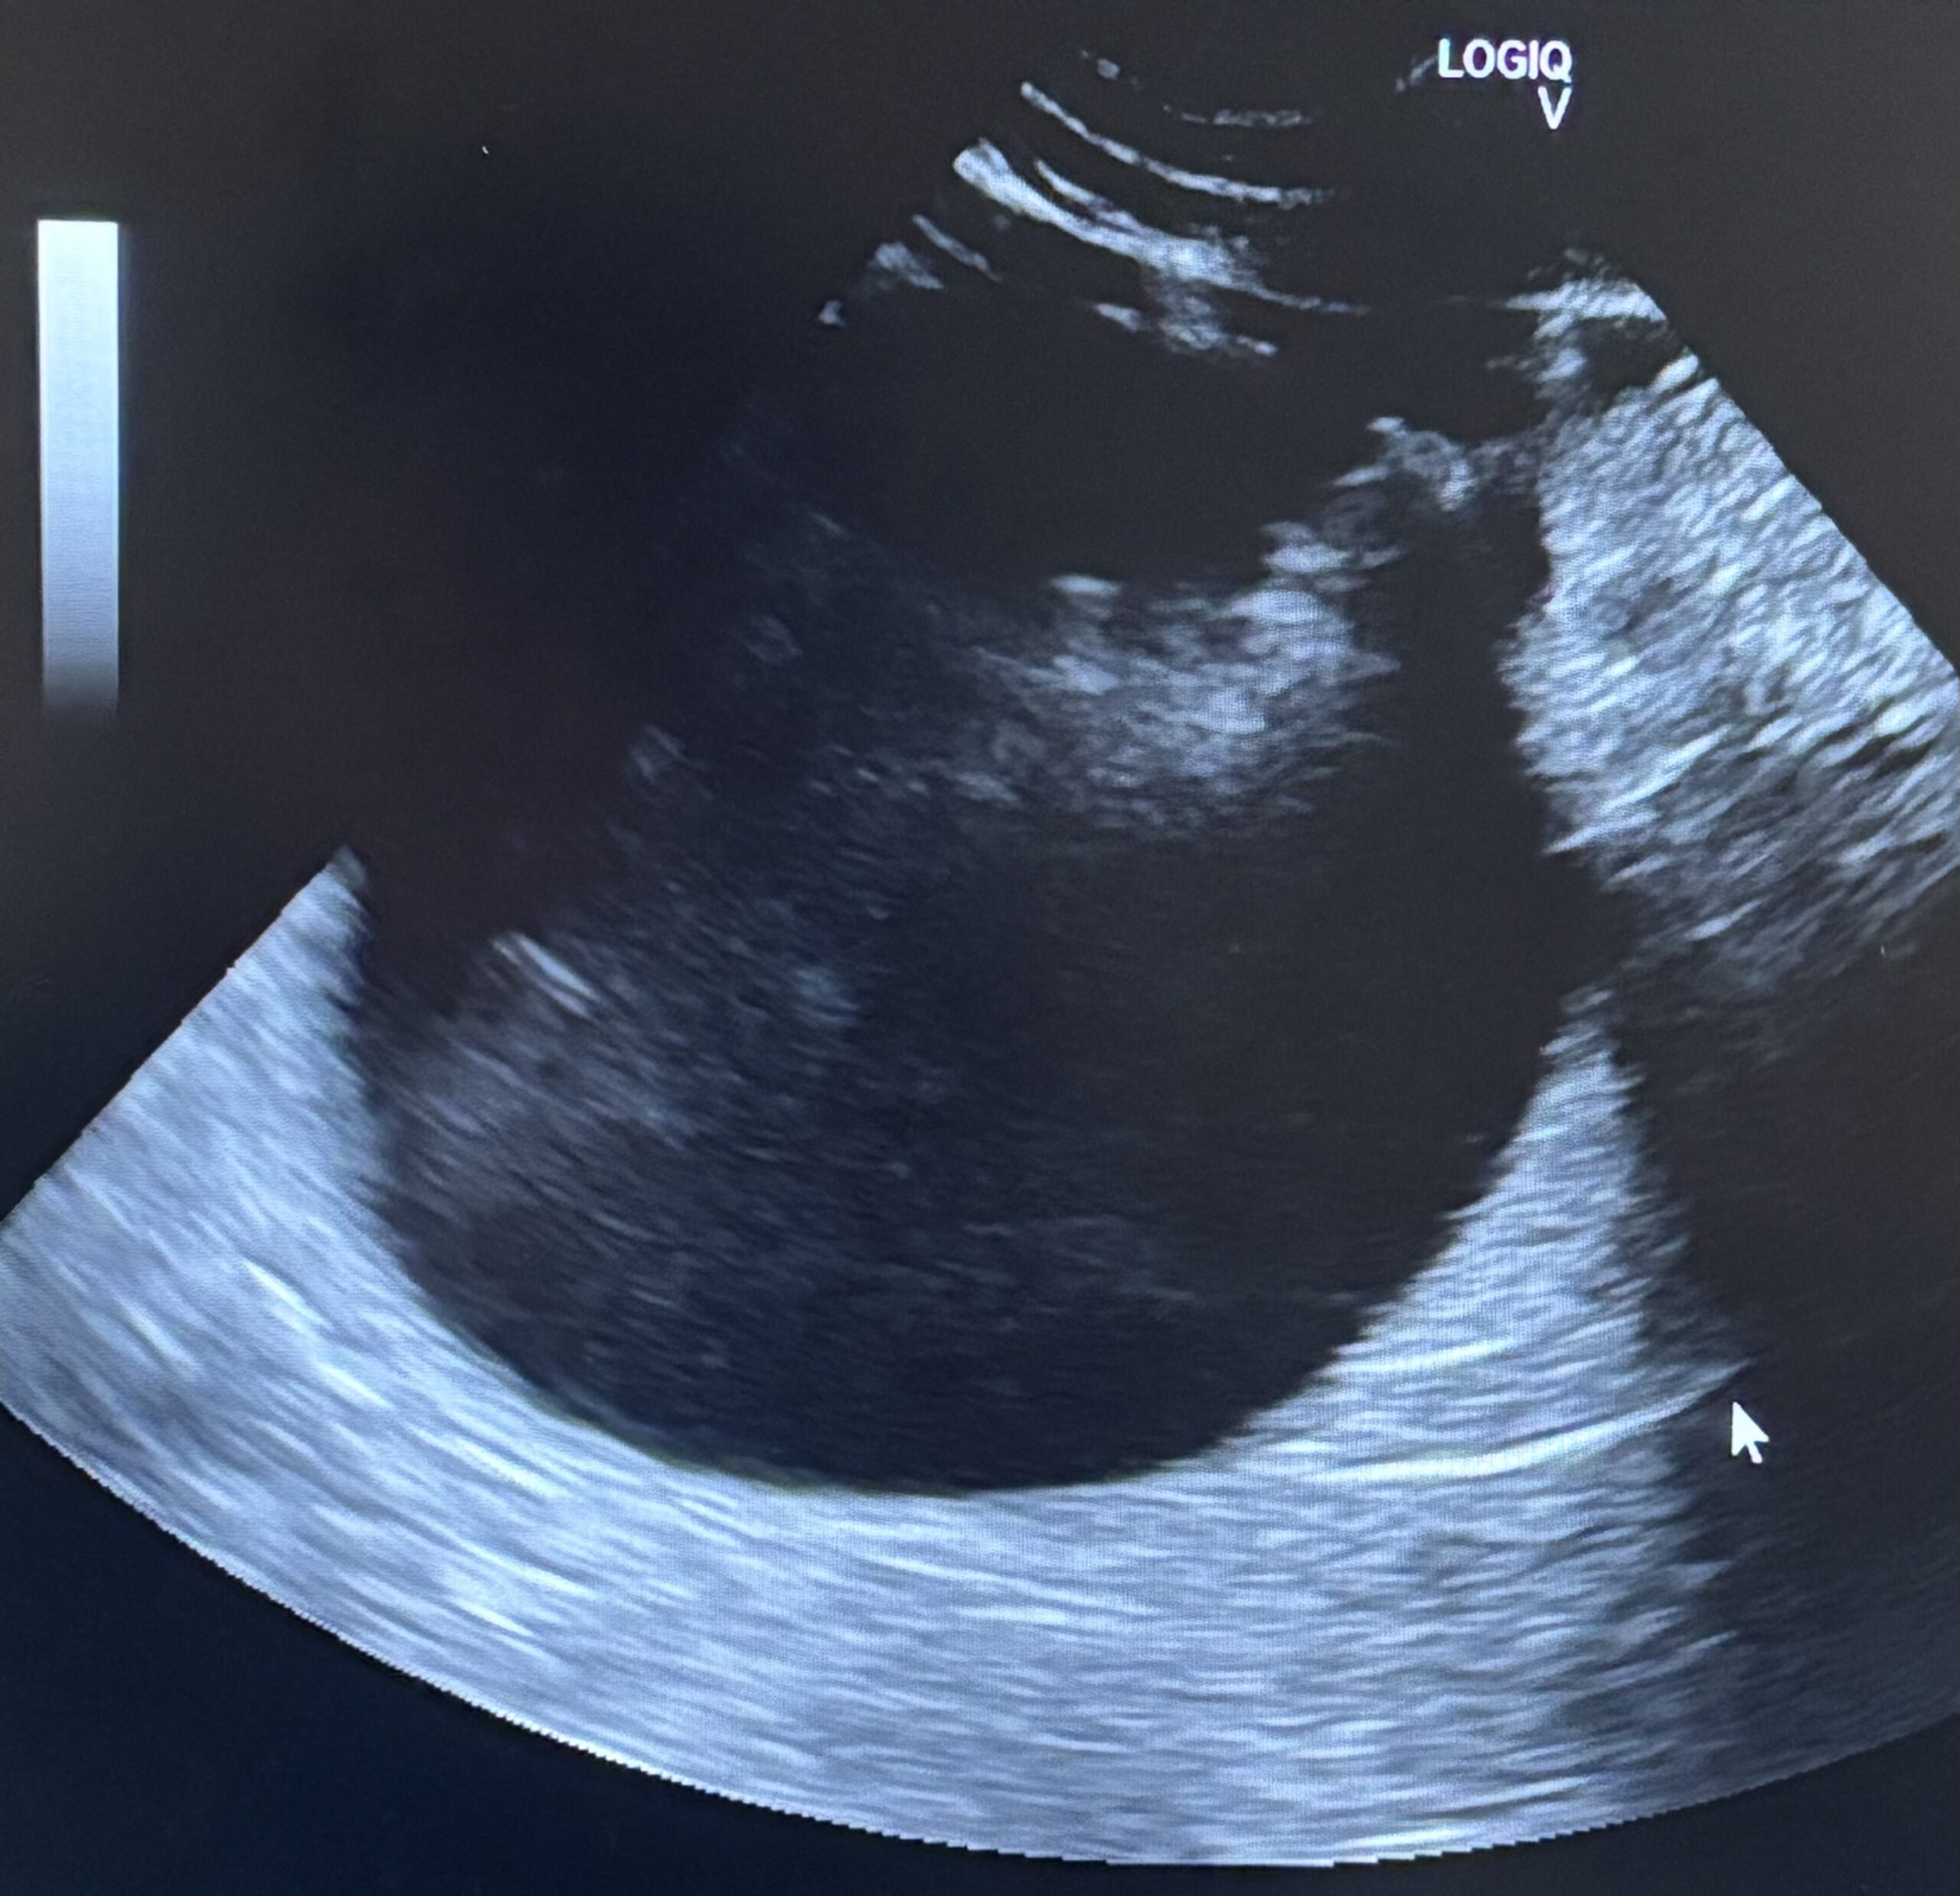

術前の超音波検査において、膀胱は極限まで拡張し、膀胱壁は今にも破裂しそうなほど薄くなっている危険な状態でした。直ちに緊急処置として膀胱穿刺を行い、ほぼ血液成分のみの尿を80ml抜去しました。この穿刺自体、膀胱破裂を招きかねない極めて緊迫した局面でしたが、これにより一時的な減圧に成功しました。しかし、尿道先端部での物理的な閉塞によりカテーテルの通過は不可能であり、内科的解除が困難であることから、直ちに外科的介入によって尿路を確保する適応と判断しました。